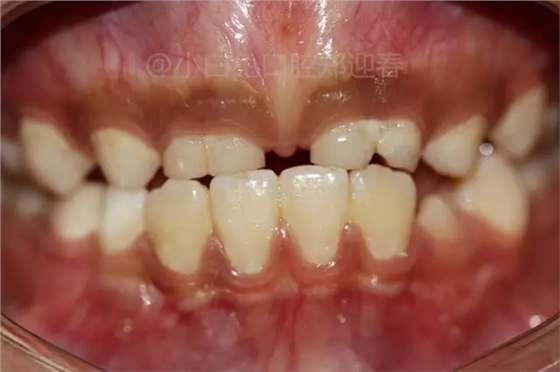

患兒,10歲,因上前牙未替換來診,查體:輕度反合,51和52、61和62均融合,且存在間隙約4mm,全面曲面斷層片顯示:11、21未萌,52、51、61、62牙根均有不同程度的生理性吸收。